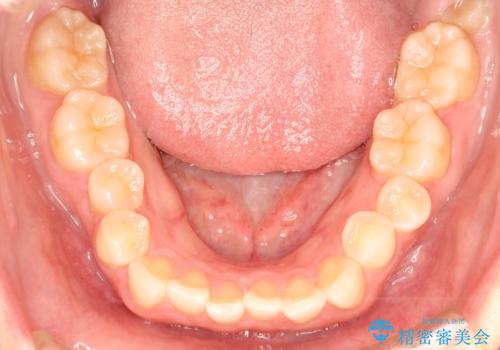

- 前歯のガタガタを綺麗にしたいとのことでインビザラインにて治療を行いました。

治療前は臼歯部反対咬合のため下顎が偏移し正中がずれていましたが、臼歯部反対咬合を改善したことで、正中のズレを改善することができました。